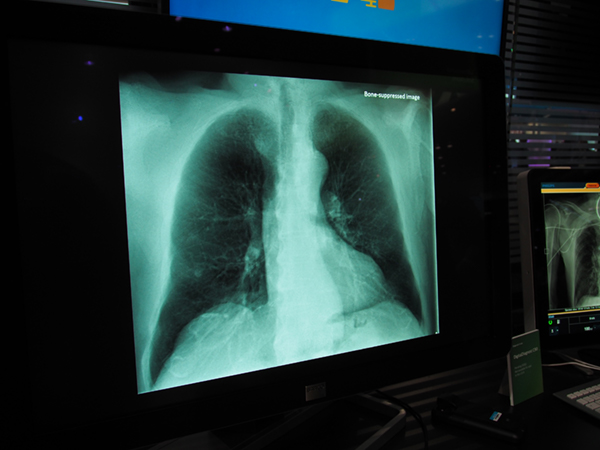

DigitalDiagnost C90には,以前より研究が進められていた骨抜きの画像処理アプリケーション“Bone Suppression”(国内薬機法未承認)も搭載可能となる。Bone Suppression画像では,肺野の病変検出率が16.8%向上するとの研究結果も報告されており*,診断能向上に寄与することが期待される。

* Freedman, M., et al.:Lung nodule;Improved detection with software that suppresses the rib and clavicle on chest radiographs. Radiology. 260・1, 265~273, 2011.